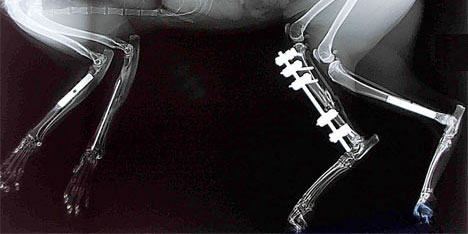

Radyoloji ünitemizde bulunan son teknoloji yüksek frekanslı röntgen cihazımız çekimi çok kısa sürede gerçekleÅŸtirerek, petinizin maruz kaldığı radyasyonu minimuma indirgememize olanak vermektedir.